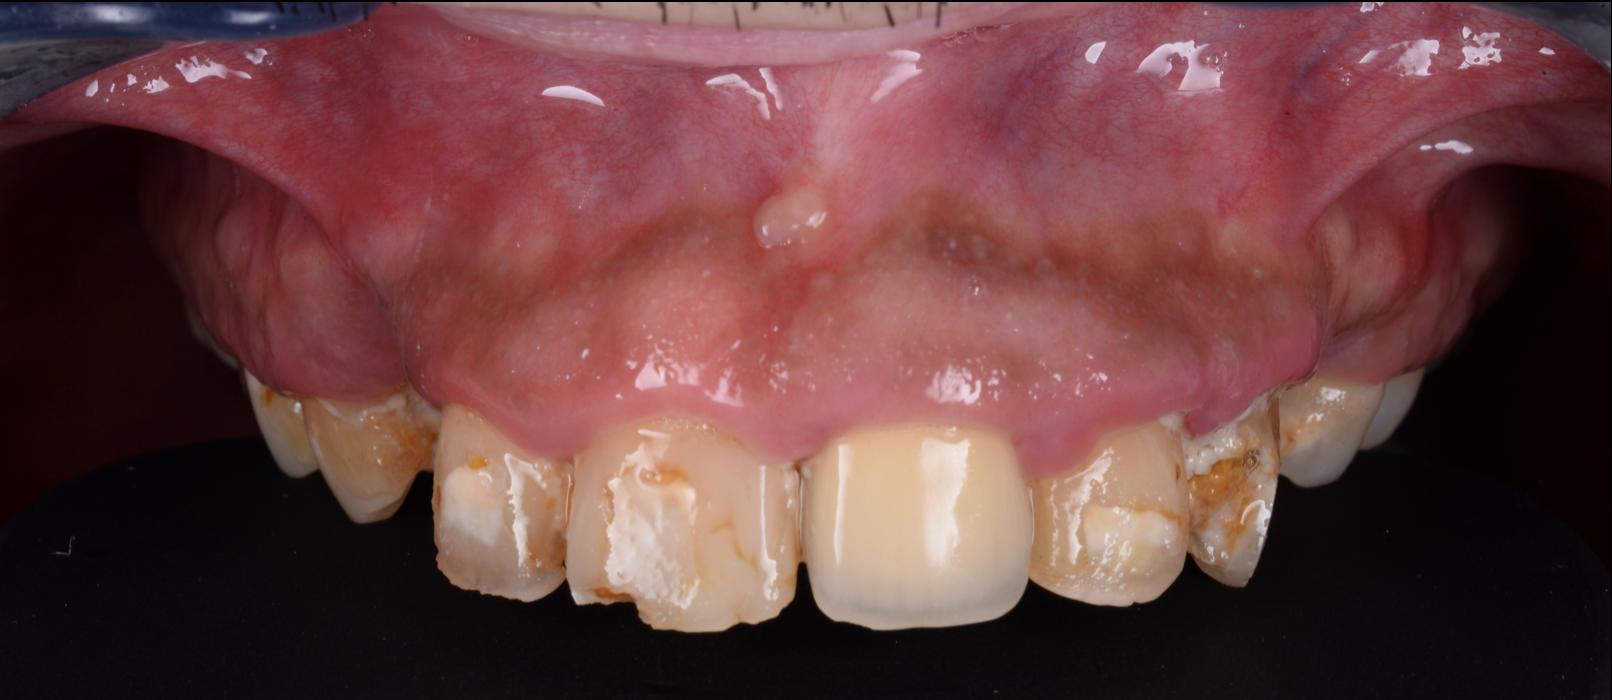

歯がボロボロでも、もう一度しっかり噛めて笑える...